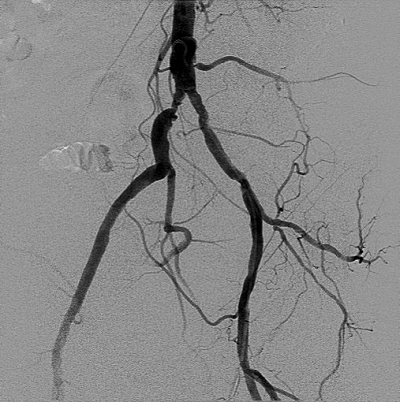

A 64-year-old man is evaluated in the office 7 days after discharge from the hospital for non–ST- elevation myocardial infarction. He was treated with percutaneous coronary intervention using a radial artery approach. Right femoral artery access was initially attempted, but the catheter guidewire could not be passed. During the procedure, an abdominal aortogram was obtained (shown). He has not had any symptoms of claudication. Medical history is significant for hyperlipidemia. He is a current smoker with a 40-pack-year history. Medications are low-dose aspirin, ticagrelor, metoprolol, and atorvastatin.

On physical examination, vital signs are stable. The right femoral pulse is faint, and a bruit is heard over the right femoral artery. No foot or toe ulceration is noted.

This patient's iliac artery stenosis could be treated safely and effectively with an endovascular approach; however, endovascular treatment of PAD is not recommended in asymptomatic patients. There is no empiric evidence that endovascular intervention prevents disease progression to intermittent claudication or critical limb ischemia.